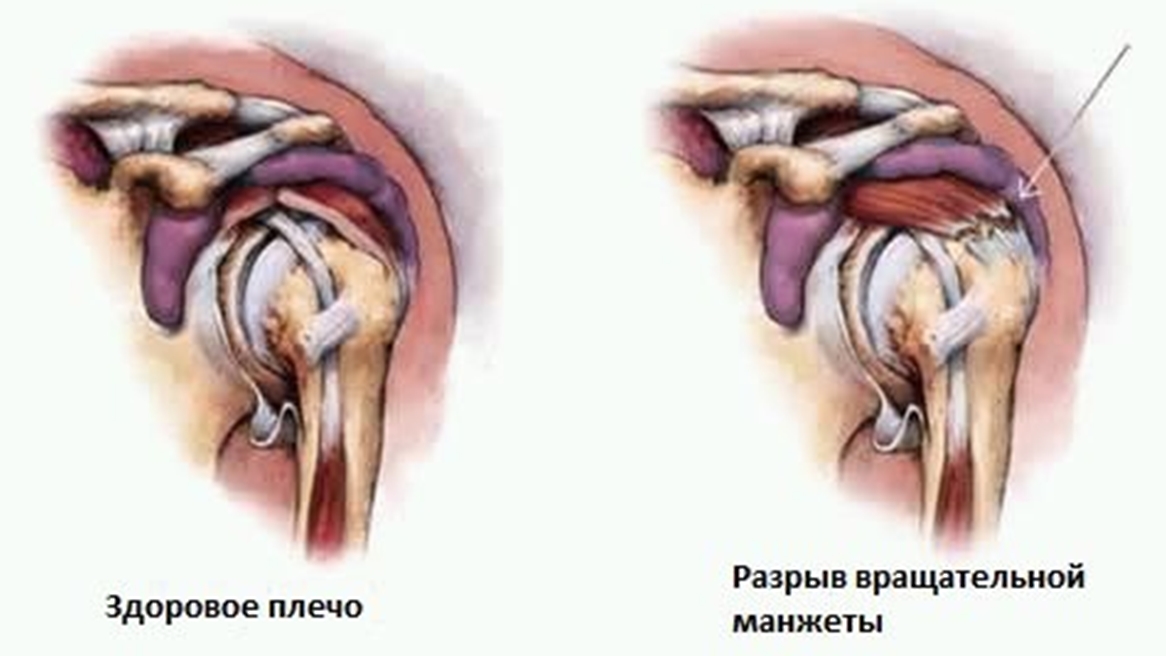

Фотографии мышц ротаторной манжеты плеча